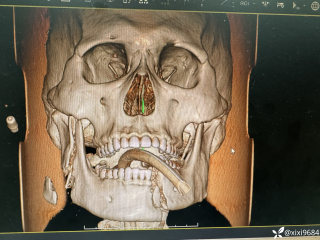

文/西地兰 特别声明:所有观点仅代表个人言论 特别声明:与当事双方均无利益相关 山东男孩,目前全网沸沸扬扬,看过一些观点,直言不讳地说,大多偏颇。要么一股脑地指责医方的全责,甚至有说千万别在县医院看病。要么又为医方无休止的遮羞,认为这样的手术在县医院做下来已经非常了不起。而我想到的是,以后面临类似的病例,我们怎么办?那么我们不如来一次专业的病案讨论。既然是事后讨论,难免有事后诸葛亮的感觉,但是假如下一次,同行们遭遇这样的病例,如何处置?这是医疗行业所面临的问题。希望我整理的这些思路和相关病例,对同行们有所帮助!就目前的资讯外界不足以判断是否需要急诊,如果需要急诊,那么只能根据术中所见进行处理,